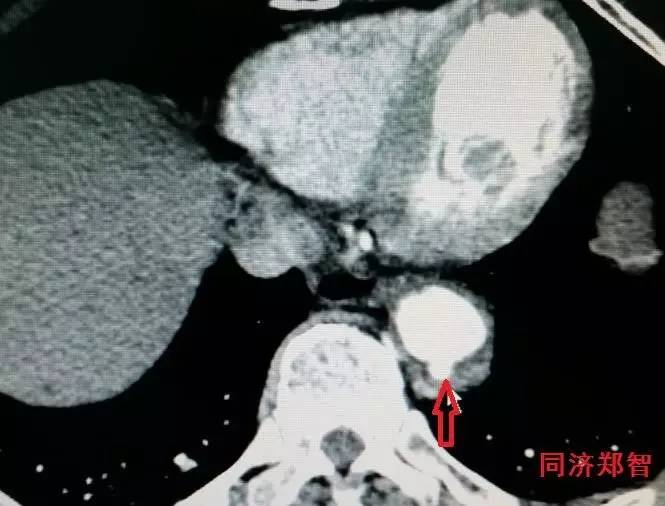

胸降主动脉穿透性溃疡合并壁间血肿(图6),心底层面红箭头所示。

图6